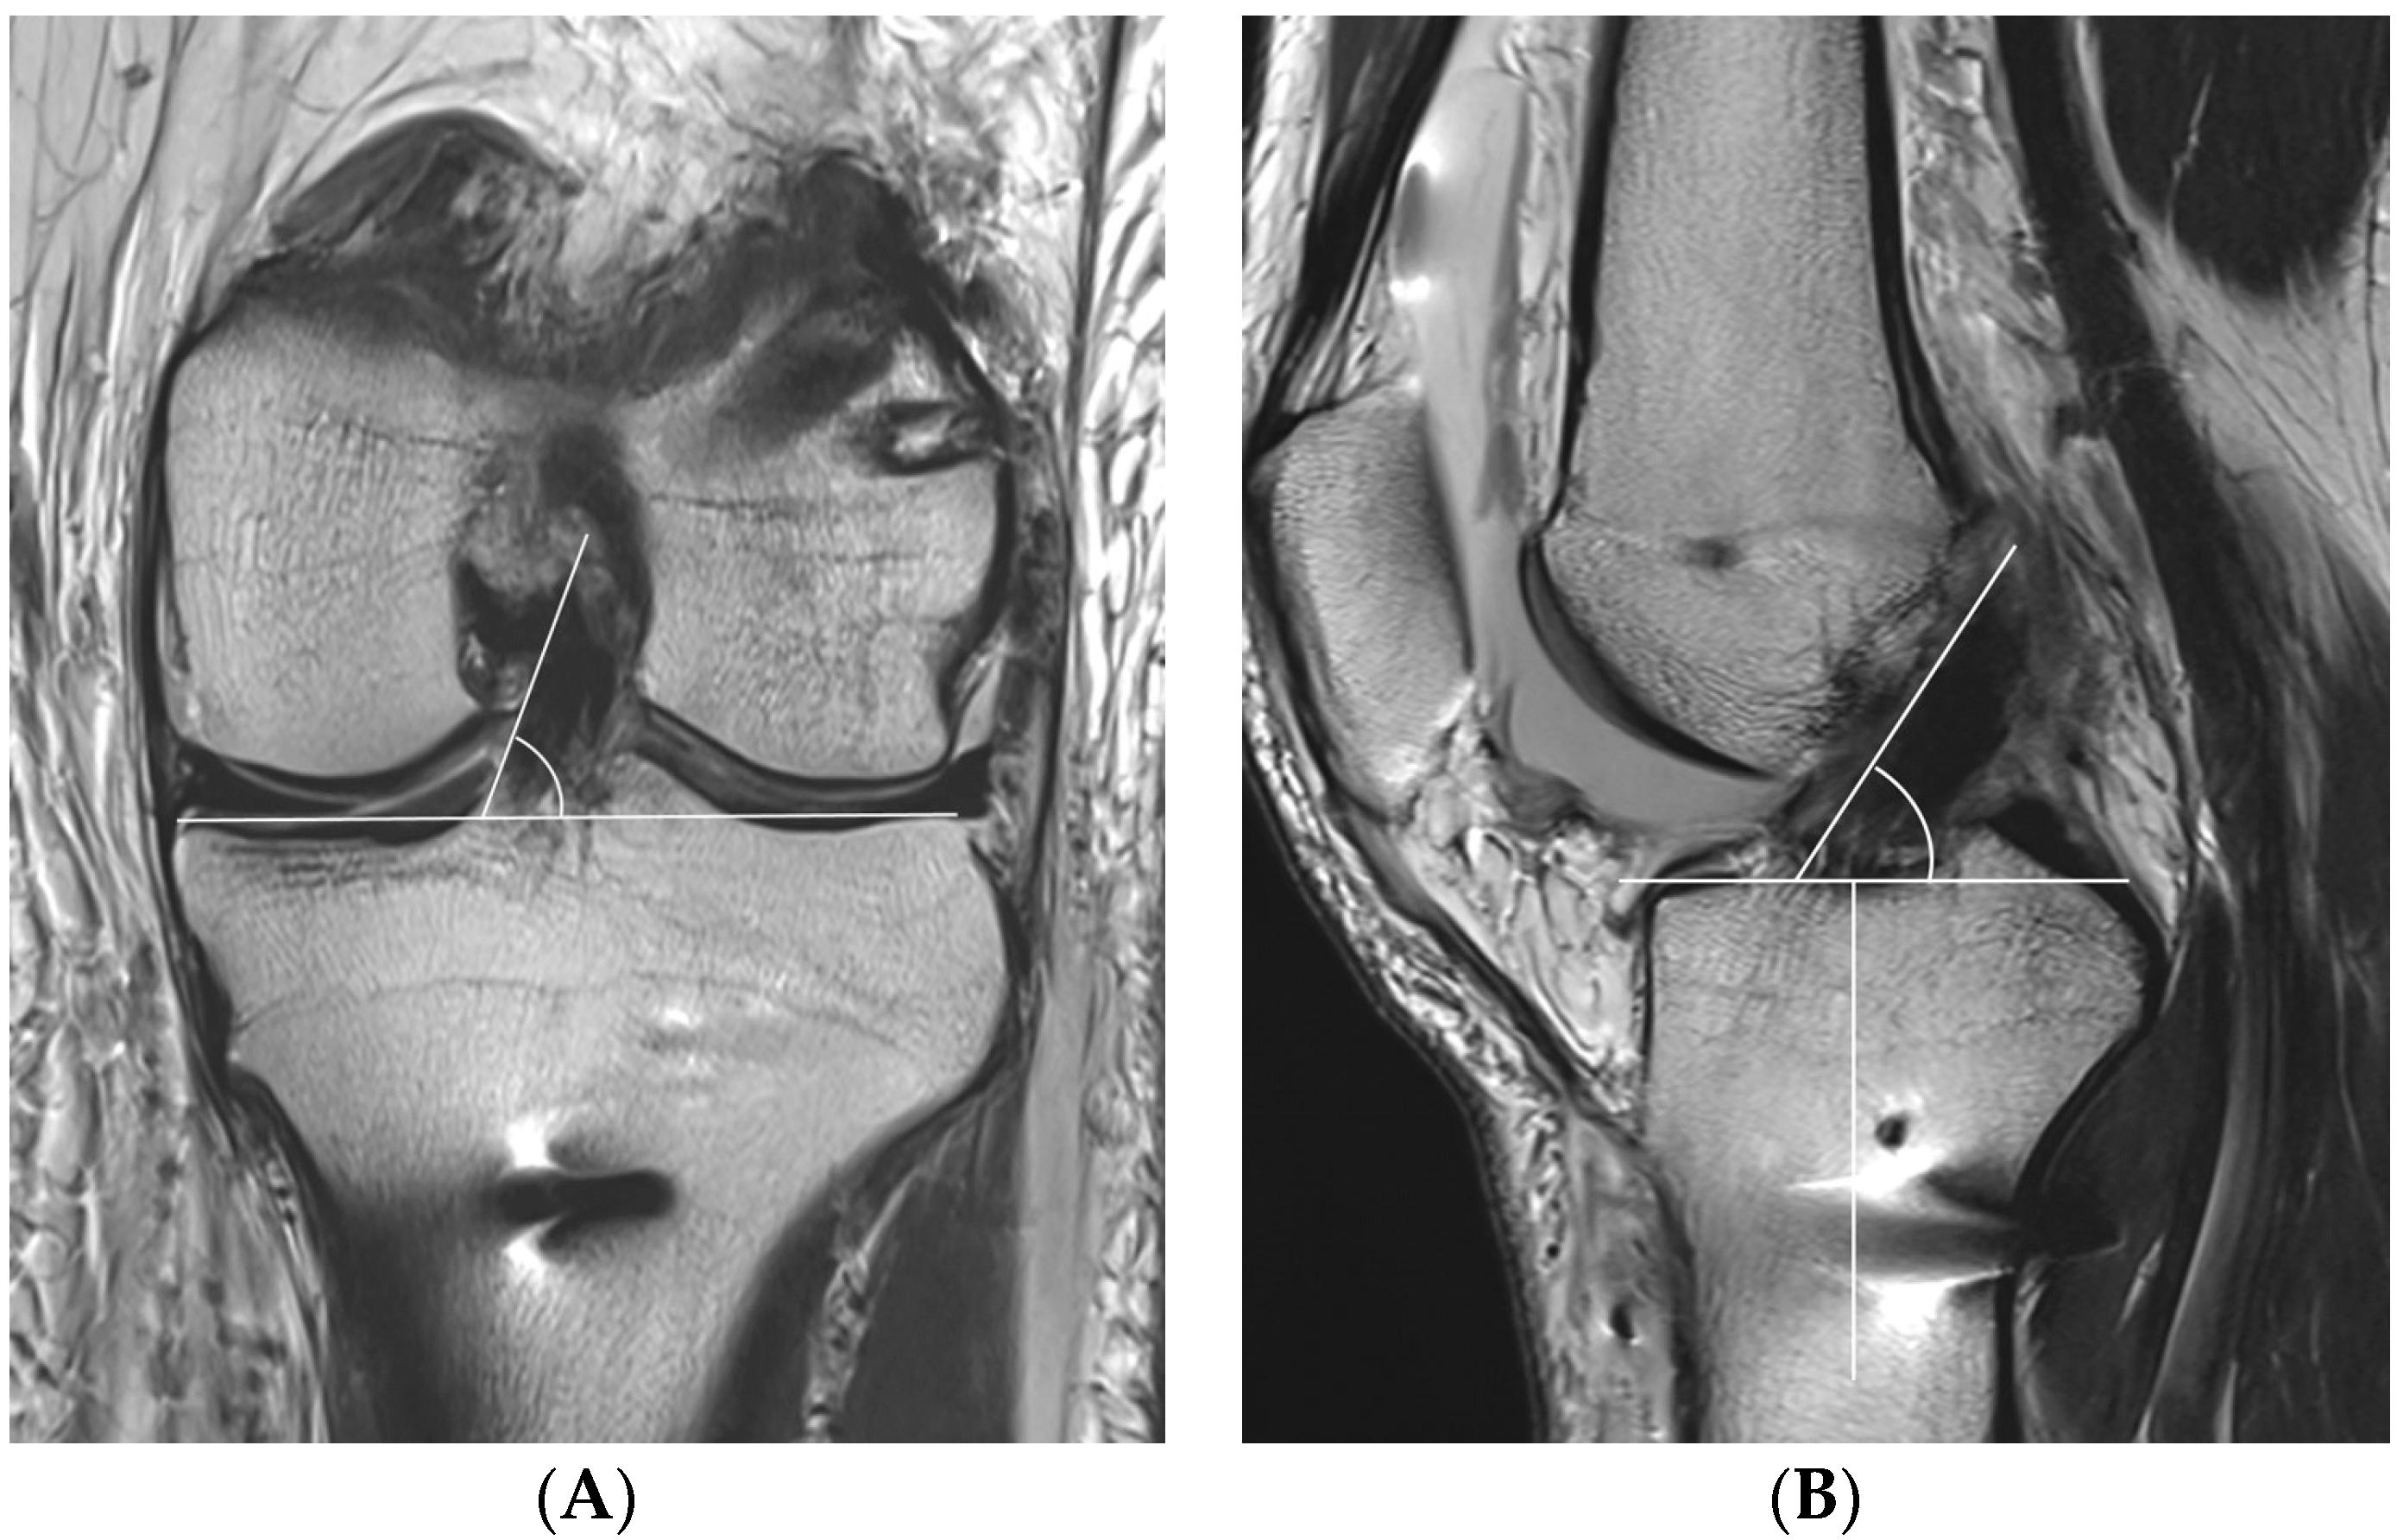

One day after ACLR, all patients underwent MRI with a 3.0-T system apparatus (Signa HD, GE Healthcare; Milwaukee, WI, USA) to evaluate for graft inclination. The graft inclination on the coronal plane was defined as the angle between the medial margin of the ACL graft through more than one slice and a line parallel to the tibial plateau at the level of the middle of the medial collateral ligament (Figure 5A). Because the entire ACL graft is unable to be visualized on one slice, if the medial margin of the ACL graft is marked and scrolled while watching the monitor, a line can be clearly drawn. The graft inclination on the sagittal plane was defined as the angle between the anterior margin of the ACL graft and a line perpendicular to the long axis of the tibia at the level of the Blumensaat line (Figure 5B).

Figure 5.

The coronal graft inclination (A) is defined as the angle between the medial margin of the anterior cruciate ligament (ACL) graft and a line parallel to the tibial plateau at the level of the middle of the medial collateral ligament. The sagittal graft inclination (B) is defined as the angle between the anterior margin of the ACL graft and a line perpendicular to the long axis of the tibia at the level of the Blumensaat line.